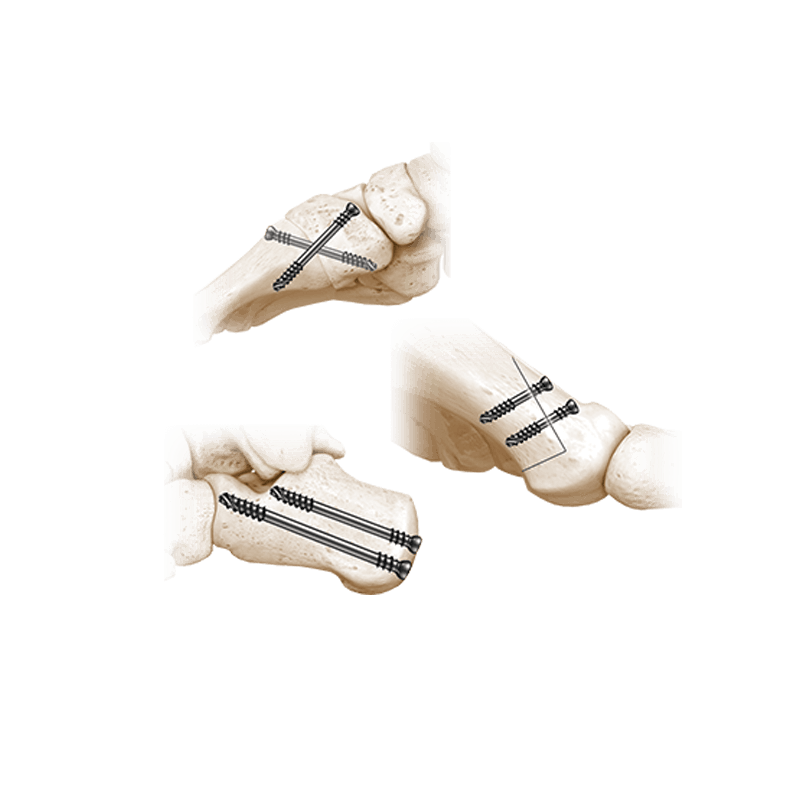

Fixation Devices - Compression Hardware

IBS™-B Beveled Screw System

IBS™-B Beveled Screw System delivers the strength, control, and versatility your MIS workflow demands.